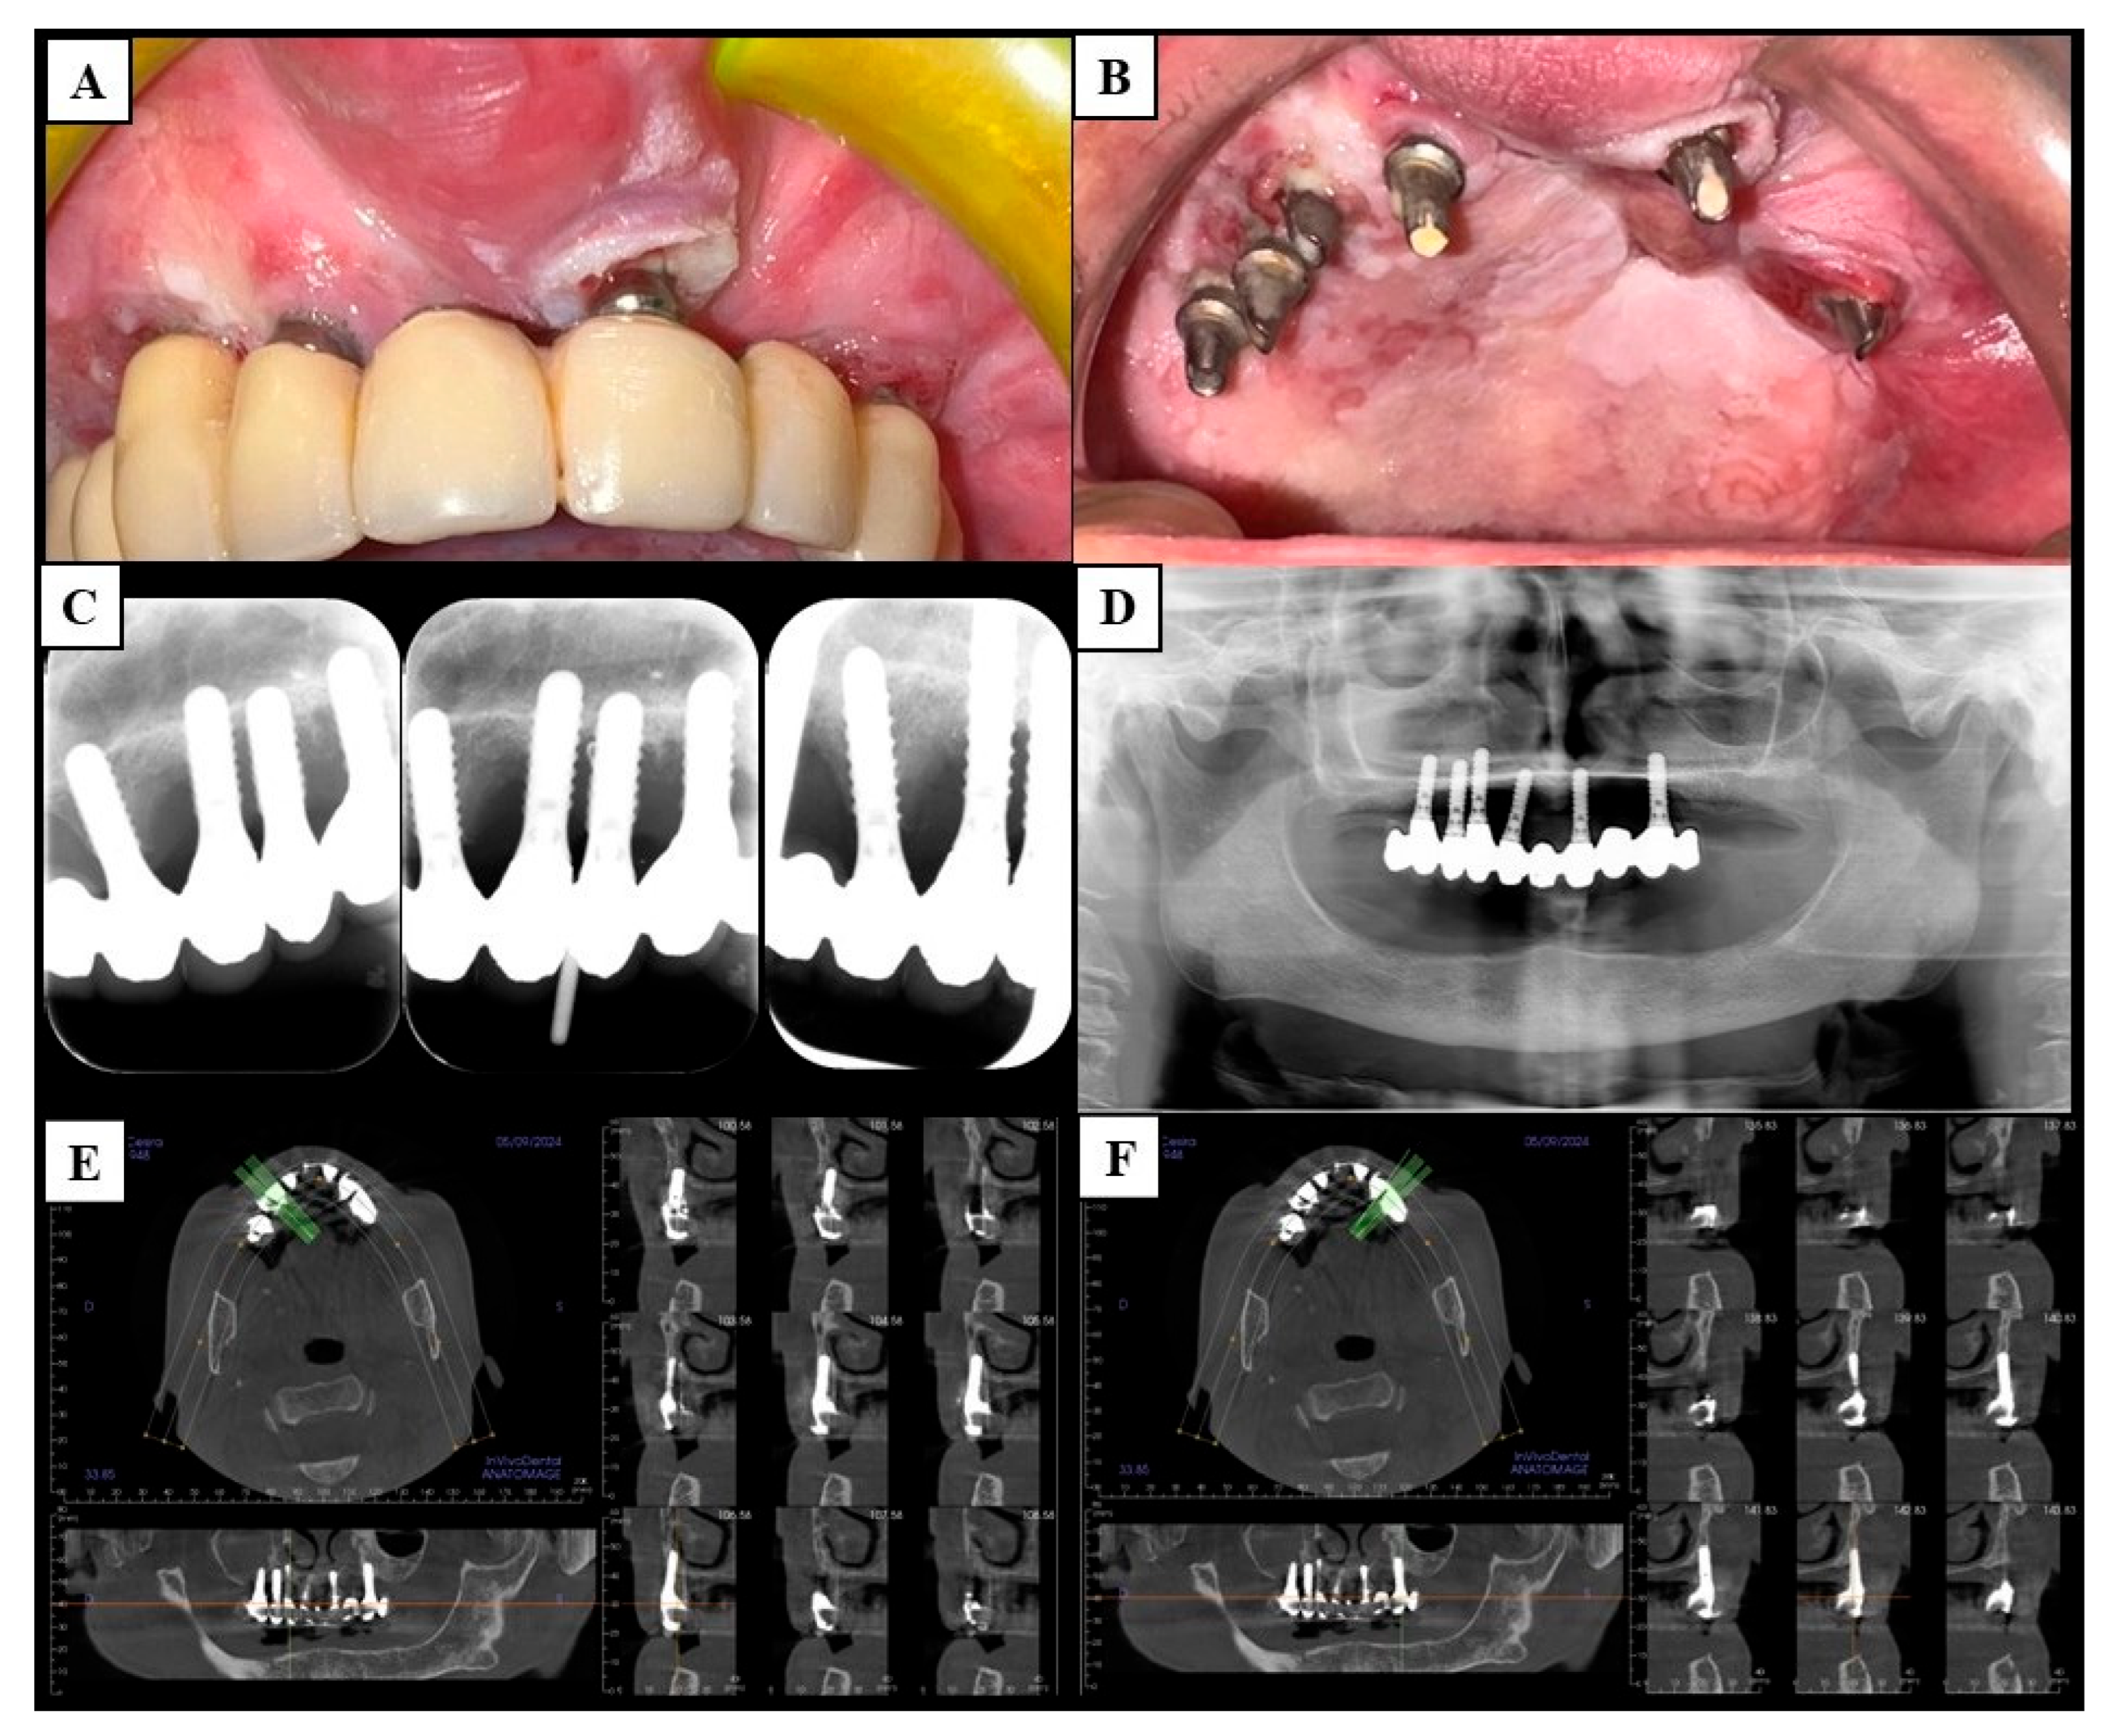

| Clinical Examination | Use vital stainings (toluidine blue and Lugol’s solution) to study erythroplakia-like and exophytic mixed lesions of peri-implant mucosa. |

| Consider as suspicious all lesions persisting after two weeks from the decontamination of peri-implant pockets. | |

| Imaging | Use scattering-free methods, such as intraoral radiograms and magnetic resonance imaging, to study the bone associated with suspicious peri-implant lesions. |